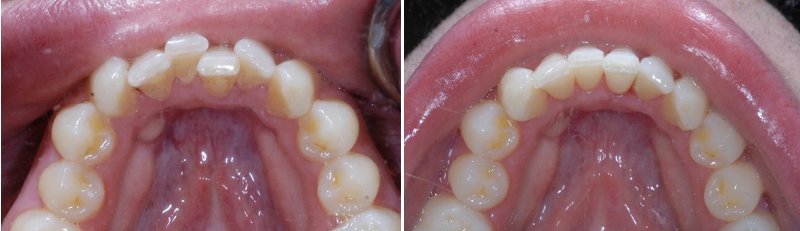

儿童牙齿拥挤矫正前后对比

1、前牙轻度拥挤的儿童,畸形一般不显着。严重的拥挤,唇部会出现不规则的畸形。牙齿在牙弓上互相重叠、拥挤,两侧不对称,中线偏向一侧,在人们的印象中常留下口歪唇斜的错觉。

2、前牙拥挤使切牙的切割能力减弱,咬合关系错乱,牙齿容易因碰撞而受伤。同时,由于牙齿的自洁能力差,刷牙也不易刷净,牙缝中常有食物残渣,容易造成龋齿、牙周炎等疾患。

3、儿童在换牙期常有前牙拥挤现象,随着颌骨发育,可以自行调整、重新排列整齐。但拥挤严重、经过较长时间还不能自行调整过来的,应及时检查,以便尽快早点采取矫治措施。